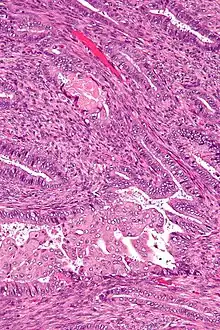

| Micrograph of an atypical polypoid adenomyoma. H&E stain. | |

APAs are characterized by glands with abnormal shapes that: (1) often have squamous metaplasia, and (2) are surrounded by benign smooth muscle.[1] Nuclear atypia, if present, is mild.

The microscopic differential diagnosis includes endometrial carcinoma and endocervical adenocarcinoma.